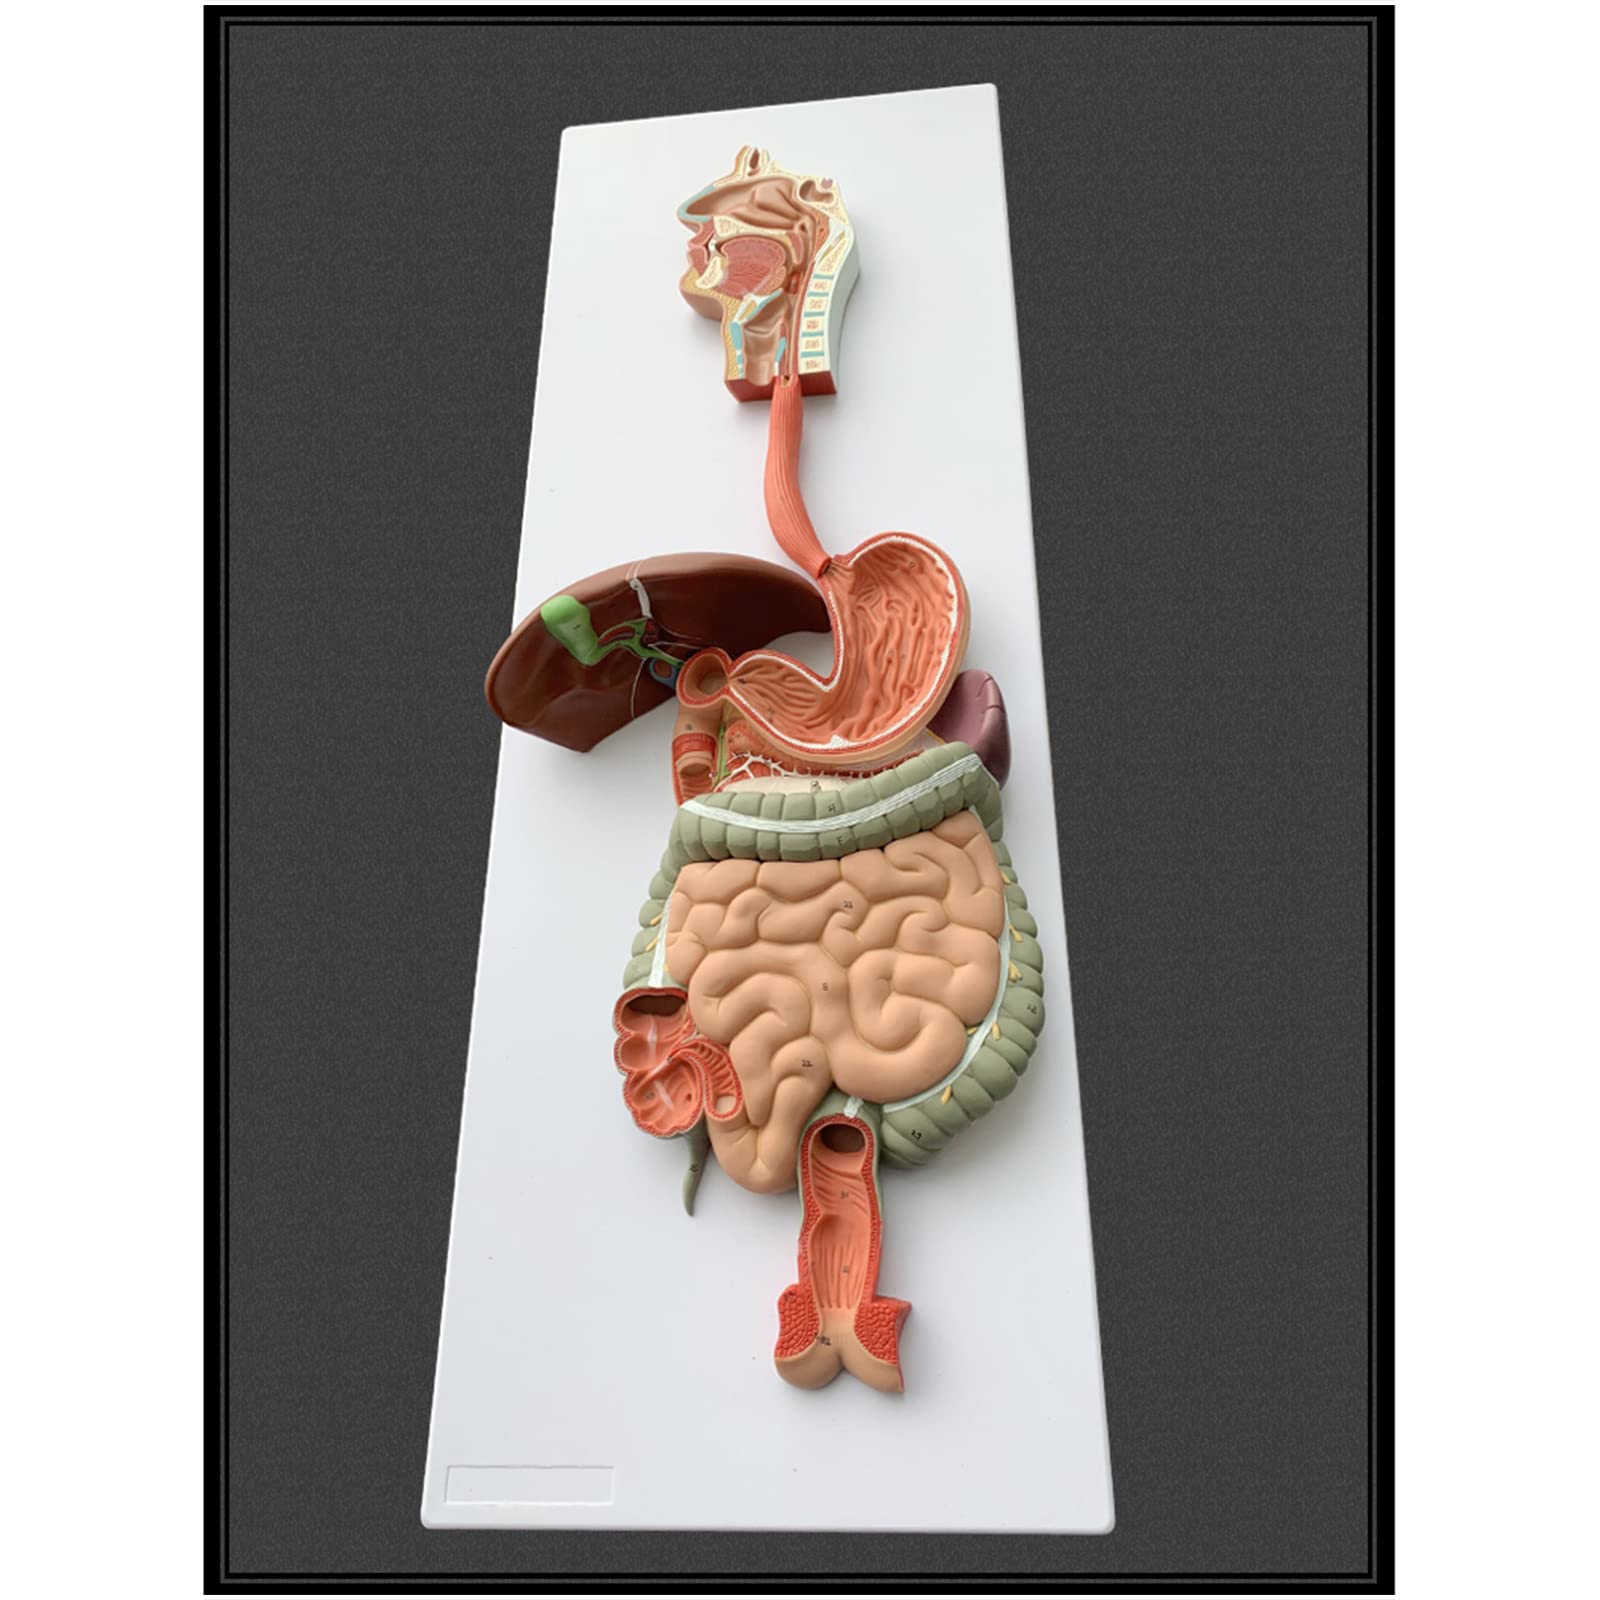

- INTERACTIVE LEARNING EXPERIENCE - Disassemble and explore the digestive system like never before!

- PERFECT FOR ANATOMY ENTHUSIASTS - Elevate your understanding of the human body with this detailed model!

- IDEAL FOR EDUCATORS AND STUDENTS - Transform your classroom into a hub of anatomical discovery!

The Human Digestive System Model is a life-size, three-dimensional representation of the human digestive tract, designed for educational purposes. It features disassemblable parts for interactive learning and is made from durable, anti-corrosive PVC material, making it an essential tool for anatomy students, educators, and healthcare professionals.